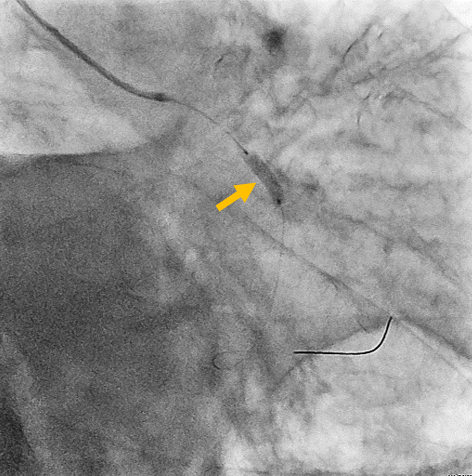

- junkankinaika-img04b-20200229